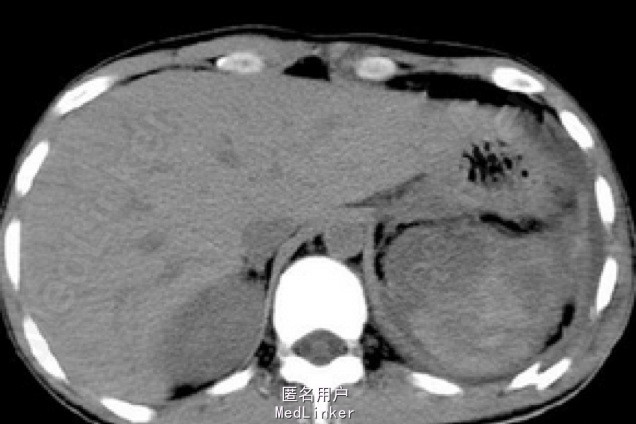

入院后,化验:血常规:白细胞:15600/mm3,嗜酸性粒细胞分数:20.3%; ESR 69 mm, CRP 176 mg/l,风湿因子:656 UI/ml,pANCA antibodies 阳性. 行肺CT:见双肺多发呈类圆形内部稍低密度影,大小不一,较大者约3.2*2.6cm(图1)。考虑肺泡出血和嗜酸性粒细胞侵润。鼻黏膜活检病理证明大量嗜酸性粒细胞侵润。根据上述,诊断为嗜酸性肉芽肿性多血管炎(EGPA,eosinphilic granulomatosis with polyangiitis)。予激素和免疫抑制剂等对症治疗。患者激素减量过程中出现咳血反复,周身及肛周出现溃疡破溃,再次与甲强龙500mg冲击后症状缓解,口腔及肛周、下肢溃烂均较前好转。进食软食一天后突然出现腹痛、发热,腹膜炎症状,查体:全腹压痛,以下腹部为重,伴有反跳痛及肌紧张。完善全腹CT检查考虑消化道穿孔(图2),EGPA并发穿孔的患者行剖腹探查,小肠穿孔修补术。术中见:腹腔小肠肠管明显扩张,多处脓苔,广泛粘连,腹腔内黄绿色渗出100ml,吸尽渗出探查,见距回盲部5cm至距TREITZ韧带150cm之间小肠多发穿孔共11处,较大者破孔3cm*3cm(图3),较小者0.4*0.4cm,予以4-0可吸收线沿肠壁横轴缝合肠壁全层及浆肌层。病理(图4):(小肠穿孔周缘)炎性肉芽组织。术后予以禁食水抗炎补液抑酸及激素治疗。术后6天因血管炎病情反复发作,出现发热,皮肤红斑,7天出现肠瘘,予以双腔套管持续冲洗接负压吸引后逐步愈合后出院。继续风湿免疫科随诊治疗。未有再次发生消化道穿孔。